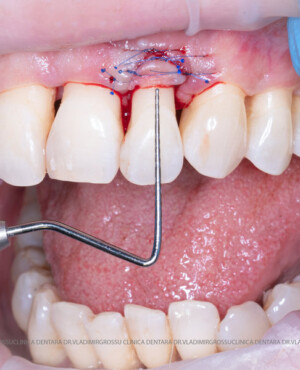

Adiția de gingie (gingivoplastia)

Aditia gingivală este o procedură chirurgicală ce corectează diverse probleme estetice și funcționale, cum ar fi recesiunea gingivală. În implantologia modernă, aditia de țesut moale este utilizată aproape în fiecare intervenție de inserție a implantului dentar pentru a asigura un aspect estetic natural și o bună integrare a implantului în cavitatea bucală.